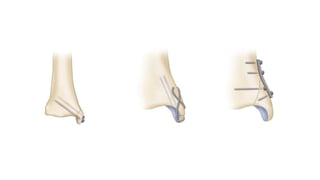

 Open reduction and plating

 plate placement

 lateral

 lag screw fixation with neutralization plating

 bridge plate technique

 posterior

 antiglide technique

o most common disadvantage of using posterior antiglide plating

is peroneal irritation if the plate is placed too distally

o posterior antiglide plating is biomechanically superior to lateral

plate placement

 intramedullary retrograde screw placement